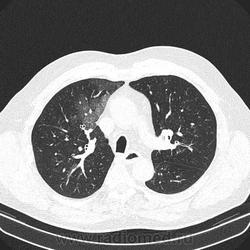

Альвеолярное кровоизлияние.

Полисегментарная пневмония.

оказалось ТЭЛА.

эту пневмонию вылечили, через некоторое время пациент поступил с подобной картиной в другом легком.